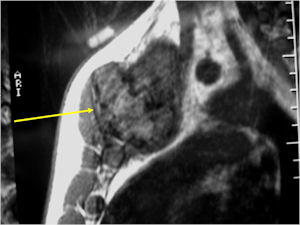

MRI:

- Also useful in determining extent

- There is often extensive edema around the tumor in the surrounding bone and soft tissues that can lead to a misdiagnosis of a malignant tumor.